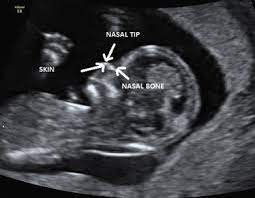

If the 2D ultrasound does not demonstrate two nasal bones then 3D ultasound may be useful. An ultrasound scan There is no risk to the baby from either of these procedures. October 15 2018 Shane Dale According to the National Down Syndrome Society NDSS during the normal fertilization of a womans egg by a mans sperm the resulting nucleus of each cell in a fetus contains 23 pairs of chromosomes half of which are inherited from each parent.

For this reason 3D ultrasound reconstruction of the nasal bone and other facial bones is useful. At this stage the babys legs arms fingers and toes should be fully formed. Mothers should not be encouraged to have an ultrasound called a.

An ultrasound can detect fluid at the back of a fetuss neck which sometimes indicates Down syndrome. During the first trimester this combined method results in more effective or comparable detection rates than methods used during the second trimester.